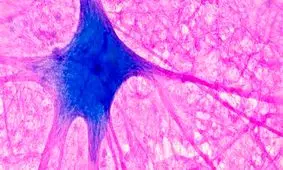

مغز شما هم مانند بقیهی اعضای بدنتان نیازهایی دارد که اگر نیازهای مغزتان را برآورده نکنید، به احتمال زیاد کارهایی را…

متخصصان علوم پزشکی میگویند تاثیر چاقی بر وضعیت سلامت مغز و «عملکرد شناختیِ» آن تایید شده است اما آثار بلندمدت الگوهای…